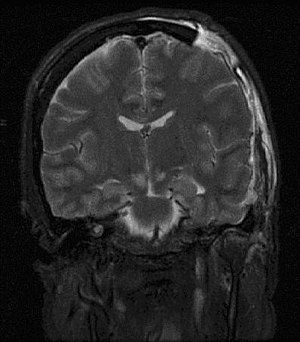

| Severely high ICP can cause the brain to herniate. | |

One of the most damaging aspects of brain trauma and other conditions, directly correlated with poor outcome, is an elevated intracranial pressure.[8] ICP is very likely to cause severe harm if it rises too high.[9] Very high intracranial pressures are usually fatal if prolonged, but children can tolerate higher pressures for longer periods.[10] An increase in pressure, most commonly due to head injury leading to intracranial hematoma or cerebral edema, can crush brain tissue, shift brain structures, contribute to hydrocephalus, cause brain herniation, and restrict blood supply to the brain.[11] It is a cause of reflex bradycardia.[12]

Severely raised ICP, if caused by a unilateral space-occupying lesion (e.g. a hematoma) can result in midline shift, a dangerous sequela in which the brain moves toward one side as the result of massive swelling in a cerebral hemisphere. Midline shift can compress the ventricles and lead to hydrocephalus.[15]